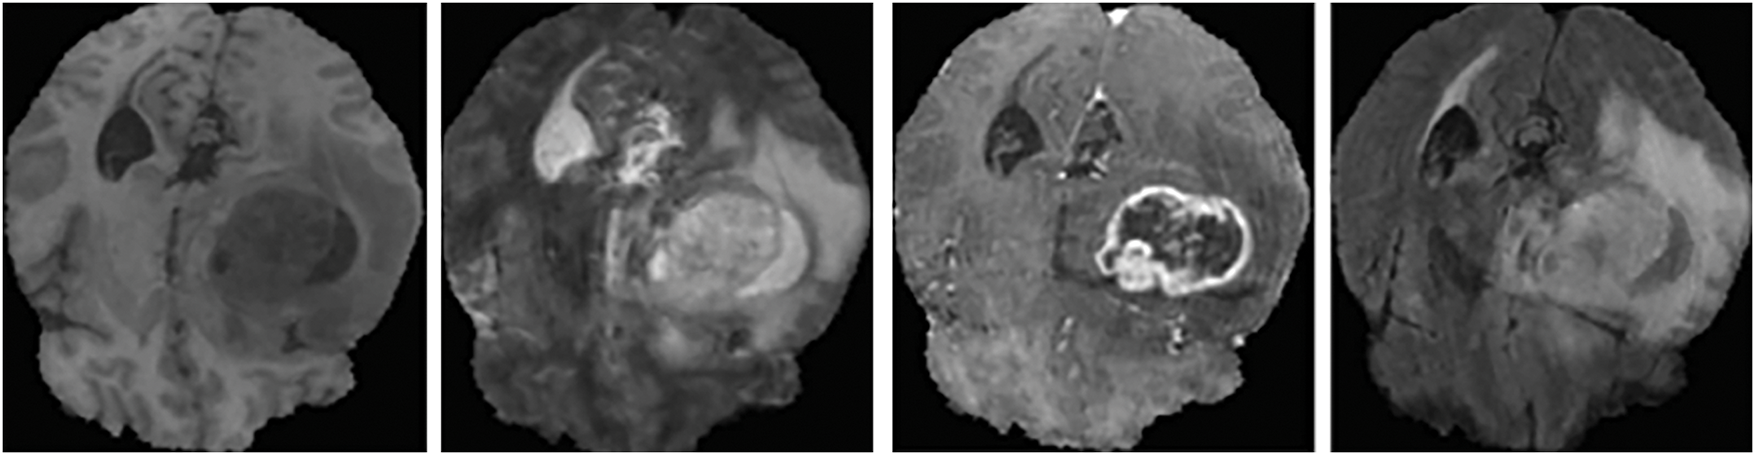

The proposed model’s effectiveness is validated on the BraTS datasets. Initially, the Dataset 1 (BraTS 2018) comprising of 75 lower and 210 higher-grade gliomas images is considered. The training dataset consists of 285 subjects with data from four modalities, while the validation dataset contains 66 subjects’ data without manual segmentation. The MRI images in Dataset 1 have pixel dimensions of 240 × 240 × 155. These MRI images are segmented by experienced neuro-radiologists. In Dataset 1, the tumor regions are classified into four types: necrosis, non-enhancing tumors, edema, and enhancing (or active) tumors [38]. A sample of the MRI brain scans from Dataset 1 is shown in Fig. 1.

Figure 1: Sample MRI brain scans of Dataset 1